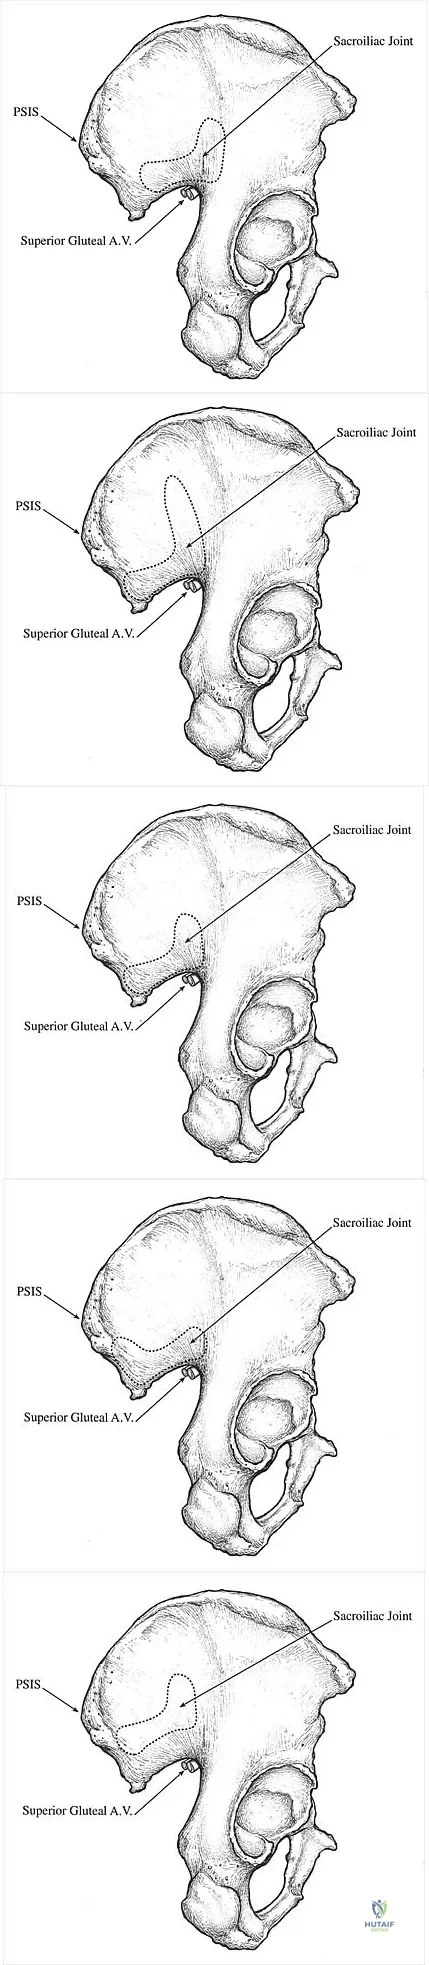

Which of the following illustrations shown in Figures 21a through 21e correctly shows the projection of the sacroiliac joint on the outer table of the ilium?